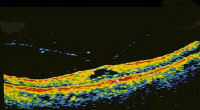

1. Match the OCT (optical coherence topography a-d ) with the most likely options

(A-N) listed below:

A. macular oedema

B. macular pucker

C. macular pseudohole

D. stage 1 macular hole

E.  stage 2 macular hole

F.  stage 3 macular hole

G. stage 4 macular hole

H. angioma

I.  macular drusen

J.  choroidal naevus

K. subhyaloid haemorrhage

L.  vitreous haemorrhage

M. pigment epithelium detachment

N.  retinoschisis

a.